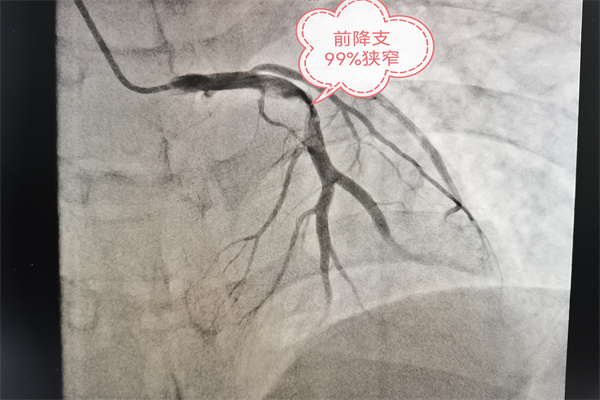

詢問后得知,患者三個月前曾因心梗在外省住院并行介入治療。經(jīng)驗豐富的心血管內(nèi)科副主任醫(yī)師尹富禹立即判定該患者很有可能為血管再梗,需要進行手術(shù)治療。緊急啟動導管室,開通綠色通道,協(xié)助患者0元辦理住院手續(xù),并繞行CCU直達導管室。冠脈造影結(jié)果顯示:左前降支近端99%閉塞。在取得患者及家屬的同意后,為其植入一枚藥物涂層支架。術(shù)后,患者的胸痛、胸悶等不適癥狀很快得以緩解。